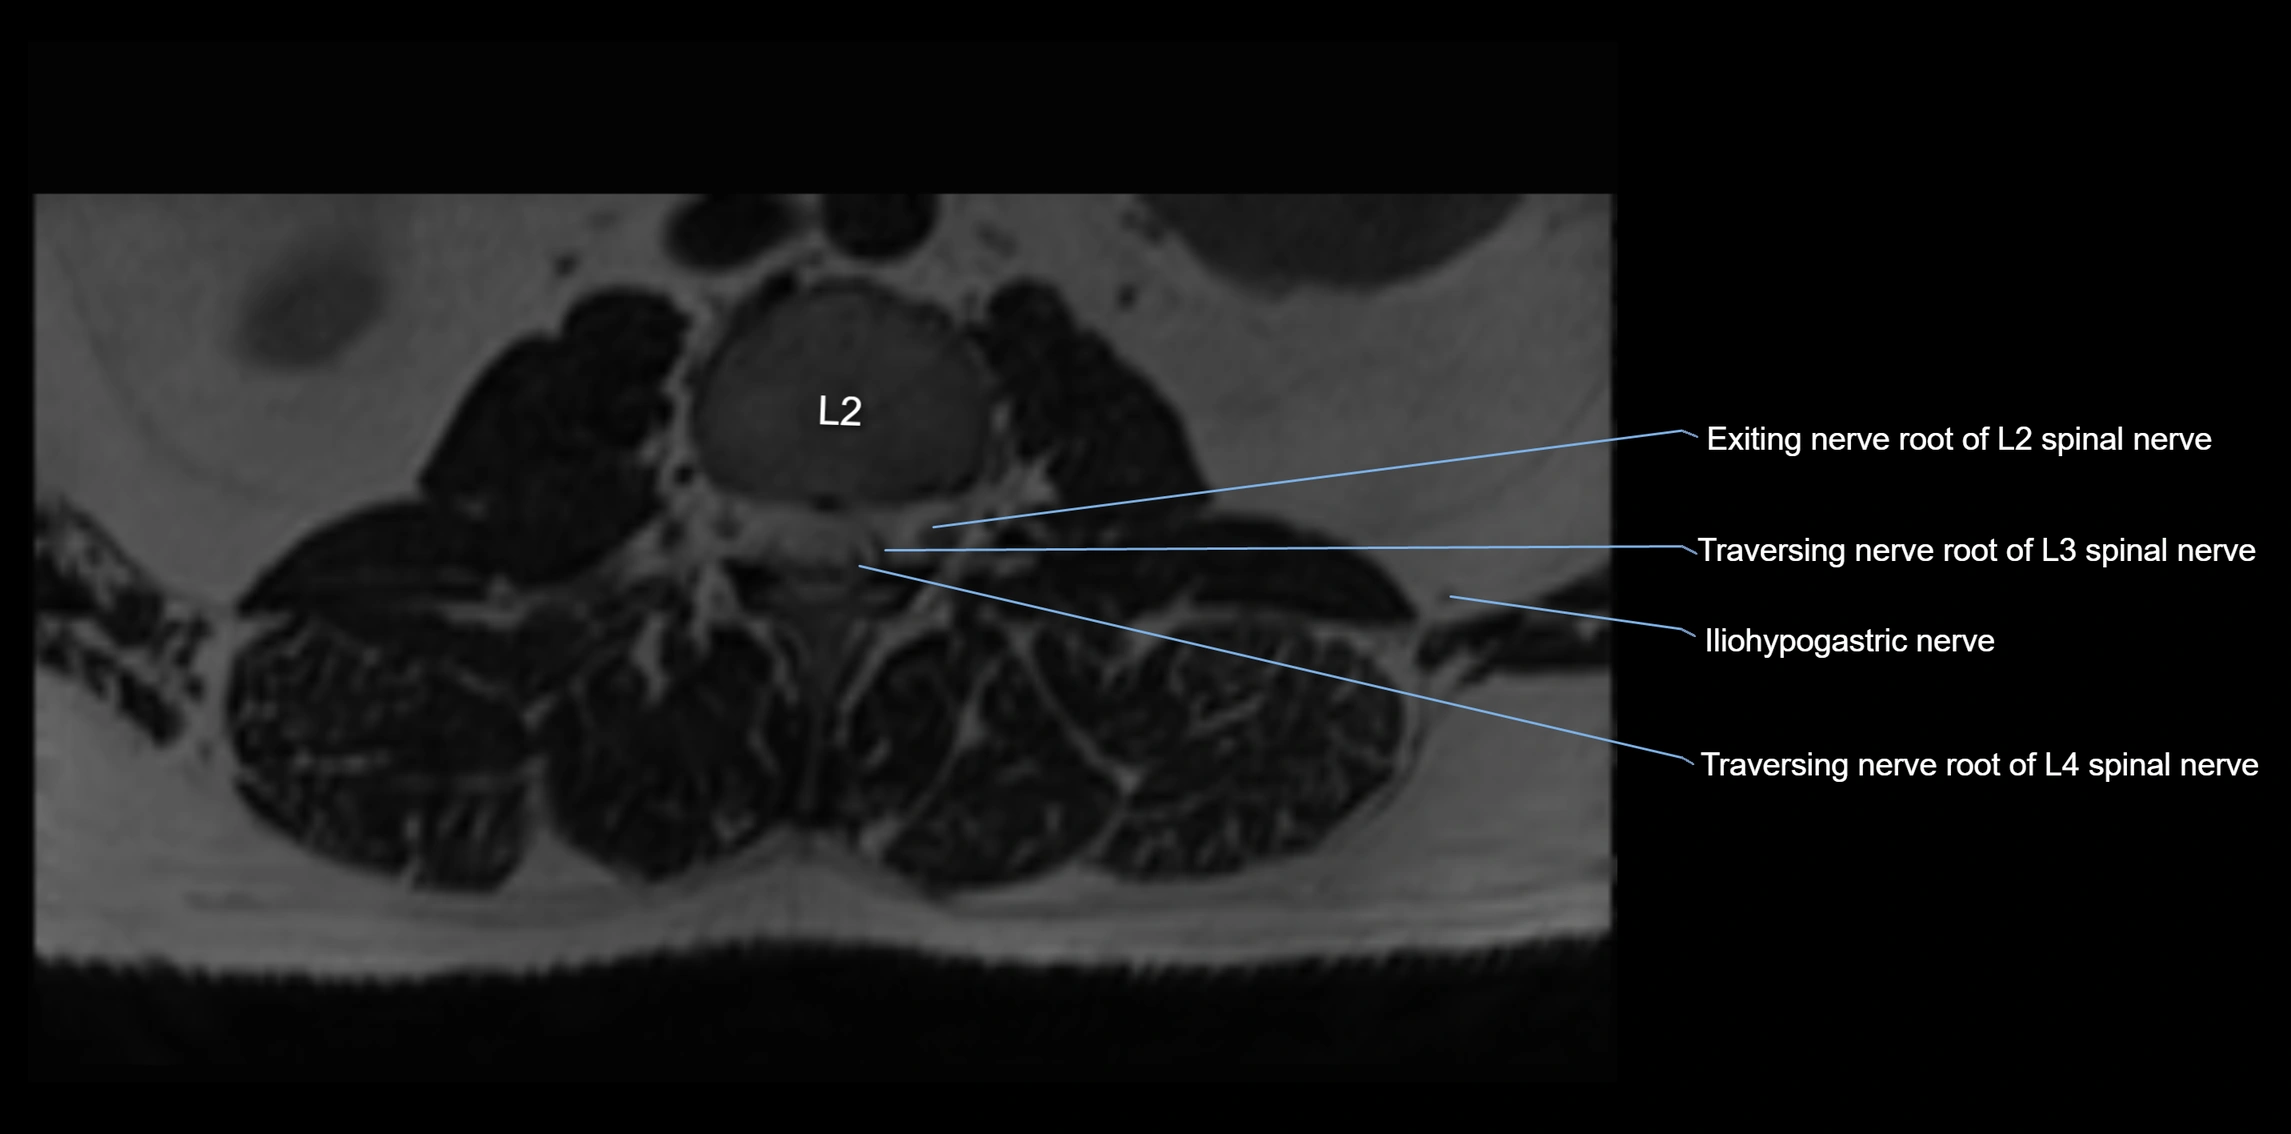

MRI image

image